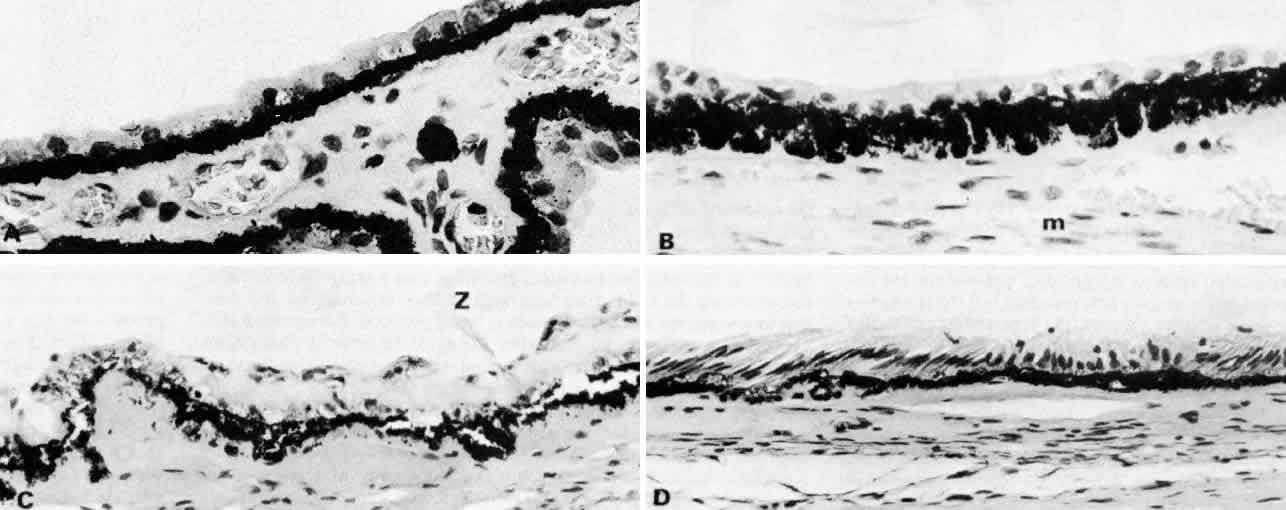

The NPE of the ciliary body stretches in a continuous layer from the root

of the iris to the ora serrata. As the transition from pigmented iris

epithelium occurs, melanin granules in the inner layer suddenly decrease

in number, and the cells become slightly smaller (Fig. 12). In the pars plicata the NPE cells are cuboidal, 12 to 15 μm in width, with

central nuclei (Figs. 13A and 13B). The knobbiness that develops during aging is due to small nodular proliferations

of NPE cells, especially on the minor plicae (Fig. 13C). In the young eye the cells of the pars plana are also cuboidal, but

with growth they become thinner and more columnar, sometimes reaching

up to 30 μm in height and 5 to 10 μm in width (Fig. 13D). In the posterior half of the pars plana, some NPE cells tilt forward

as though responding to anterior zonular traction, while others may be

inclined posteriorly, suggesting complex vectors of force in this region. The

nuclei are vertically oval and lie near the apex of the cells. The

epithelium here becomes very irregular with aging, showing hyperplastic

toothlike cell processes intertwining and extending up into the

vitreous and among the zonular fibers. At the ora serrata the ciliary

NPE joins the retina abruptly, highlighting the difference in thickness

Fig. 13. Ciliary nonpigmented epithelium. A. Anterior pars plicata, age 3. (hematoxylin-eosin, X 800) B. Posterior pars plicata with areas of thickened, pigmented

epithelium, age 3. m, ciliary muscle (hematoxylin-eosin, X 800) C. Nodular

proliferation of the nonpigmented epithelium appears

as small cellular caps over the surface at age 70. Z, zonule. (hematoxylin-eosin, X 400) D. Distorted epithelium of pars plana shows evidence

of traction in both anterior and posterior directions (adult). (hematoxylin-eosin, X 400) Fig. 13. Ciliary nonpigmented epithelium. A. Anterior pars plicata, age 3. (hematoxylin-eosin, X 800) B. Posterior pars plicata with areas of thickened, pigmented

epithelium, age 3. m, ciliary muscle (hematoxylin-eosin, X 800) C. Nodular

proliferation of the nonpigmented epithelium appears

as small cellular caps over the surface at age 70. Z, zonule. (hematoxylin-eosin, X 400) D. Distorted epithelium of pars plana shows evidence

of traction in both anterior and posterior directions (adult). (hematoxylin-eosin, X 400)